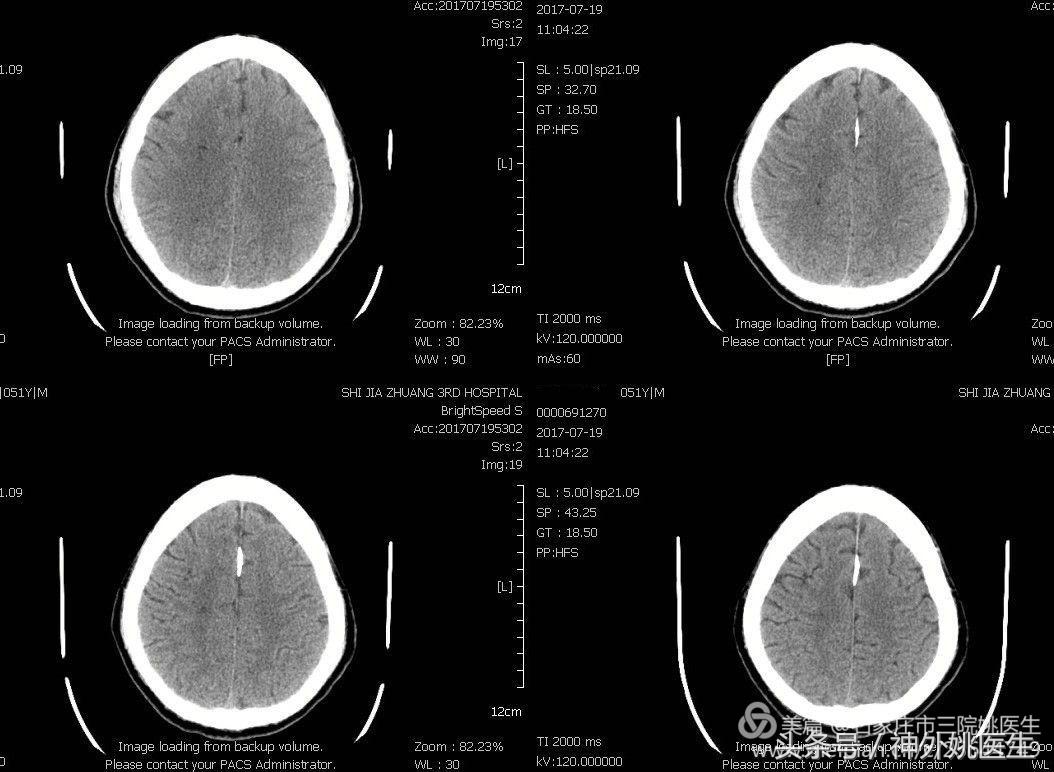

1.头CT:右额顶叶腔隙性脑梗死(图1)。

图1